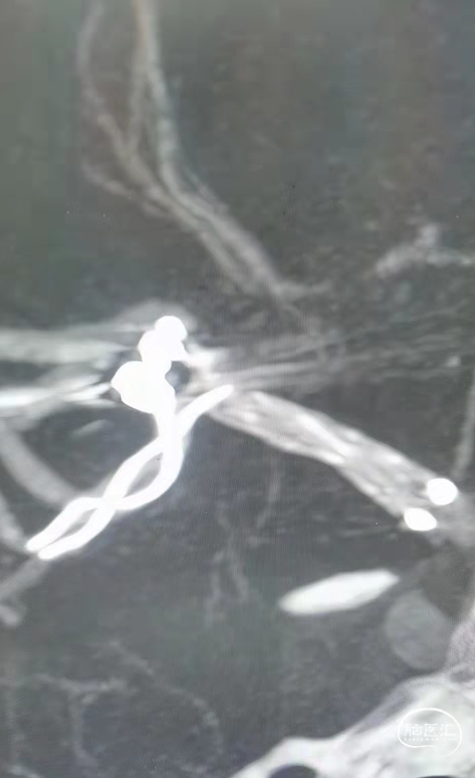

术后造影模拟血管重建显示支架头端完全覆盖动脉瘤瘤颈,并且与一期释放的支架远端形成“Kissing”。

支架:LEO+Baby支架2.5*12mm

弹簧圈:2*4-2D、1.5*2-2D

术后双容积成像显示支架头端完全覆盖动脉瘤瘤颈,并且与Solitaire支架形成“Kissing”,“T型”形成。